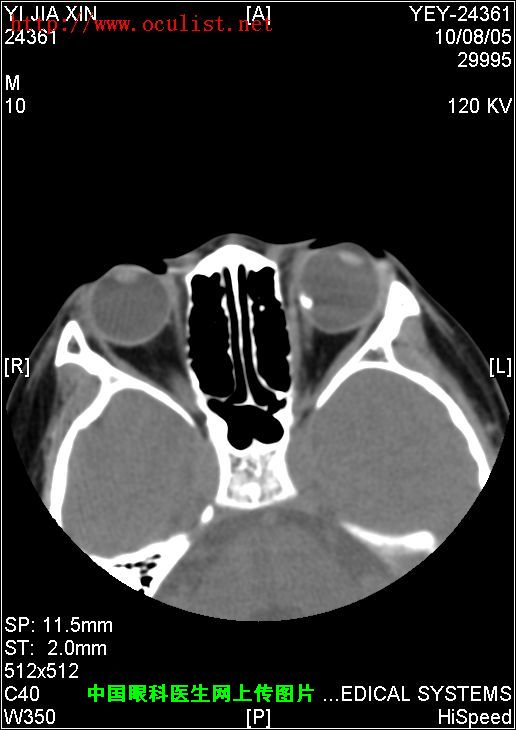

患者男,9岁,发现左眼外斜9年

患者男,9岁,发现左眼外斜9年,检查:左眼视力0.01(矫正不应),左眼外斜400,角膜、晶状体未见异常,眼底如下图,CT如下图,RMI暂无,请分析一下该患儿的诊断?

眼底图和CT片: